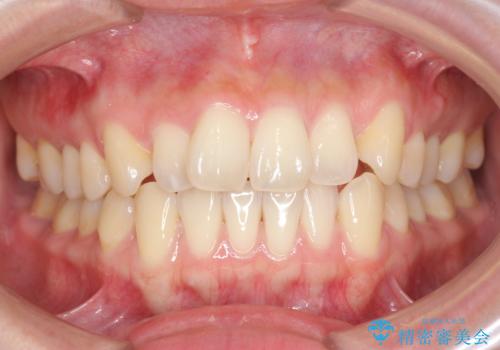

下の歯のがたつき 上より気になる

口元大事です! 見違える矯正!! 乱ぐい歯もあきらめないでください。